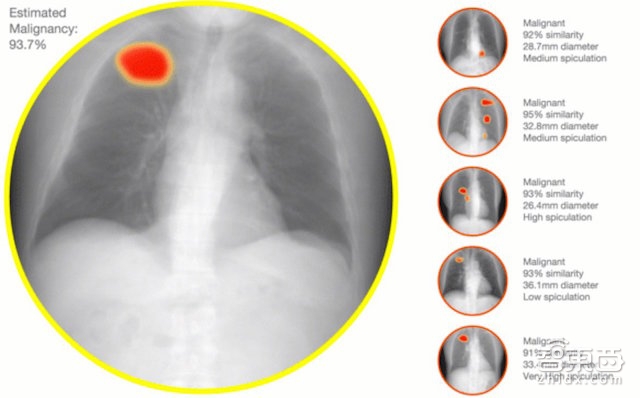

除了已经比较成熟的医疗单据识别业务之外,医拍智能目前还在拓展一条医疗影像领域的新业务线,通过深度学习、计算机视觉的技术,为放射科医生提供医疗影像(如X光、CT影片)辅助诊断,让系统告诉医生这张是肺癌病变图像,那张是良性肿块,降低医学影像漏诊率。

但由于医拍智能是专门应用在医疗领域的图文识别,因此会比一般图文识别技术存在一些挑战:比如医学术语的识别与理解、病历/化验单照片比一般图片上的文字更为模糊,纸张也会更大等等。而医拍智能最近在拓展的CT、X光等医疗影像诊断新业务线则对图像处理、识别技术提出了更高的挑战。